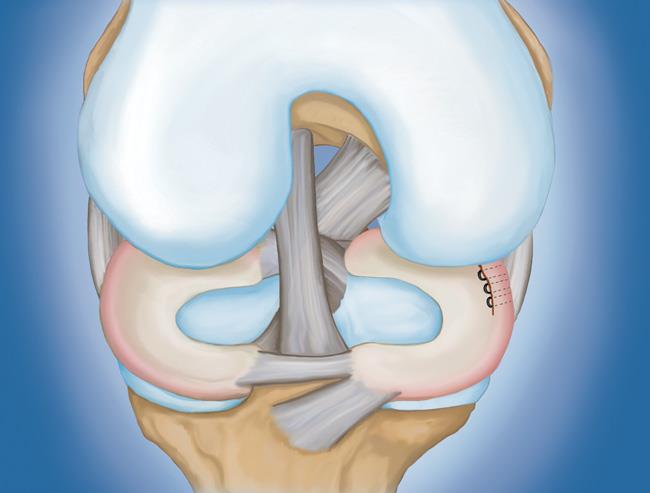

- 半月板修復。 一些半月板撕裂可以通過將撕裂的碎片縫合(縫合)在一起來修復。撕裂能否成功修復取決于撕裂的類型,以及受傷半月板的整體狀況。因為半月板必須一起愈合,修復的恢復時間比半月板切除術長。

程序。 膝關節鏡檢查是最常進行的外科手術之一。在這個過程中,外科醫生通過膝蓋上的一個小切口(入口)插入一個微型相機。這提供了膝蓋內部的清晰視圖。然后外科醫生通過兩個或三個其他小入口插入手術器械以修剪或修復撕裂。

- 部分半月板切除術。 在這個過程中,受損的半月板組織被修剪掉。該程序通常允許在手術后立即負重和全方位運動。